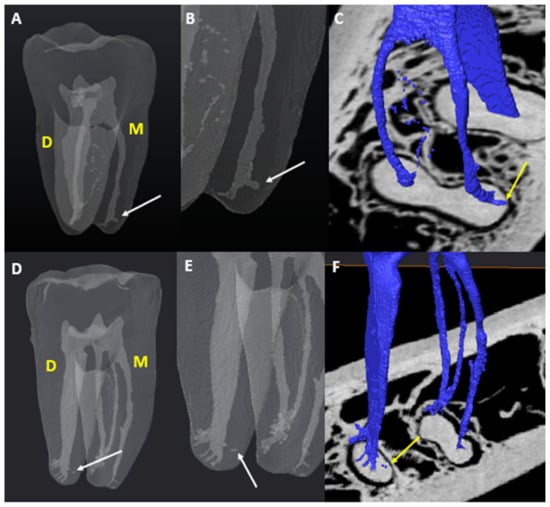

3.5.1. M Root

3.5.2. D Root